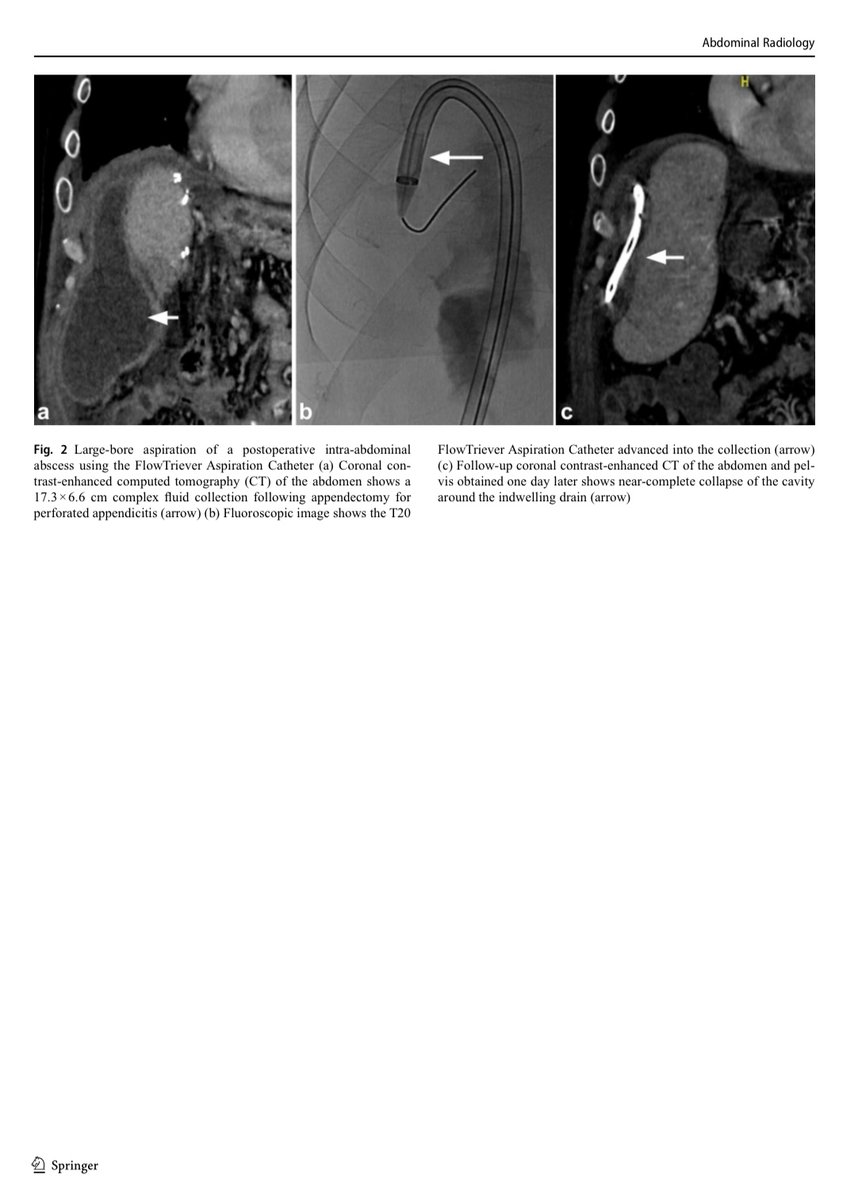

The FlowTriever aspiration catheter may be used off-label for complex non-vascular collections refractory to standard drainage, allowing effective debris removal with drain placement and potential resolution, though cost-effectiveness requires further study. @USC @InariMedical

Mechanical aspiration with the FlowTriever Aspiration Catheter may be an alternative or adjunct to catheter upsizing and fibrinolytic therapy for complex intra-abdominal abscesses, especially when drainage fails. https://t.co/hr08aRaZ8o @InariMedical @CVIR_Journal @JVIRmedia